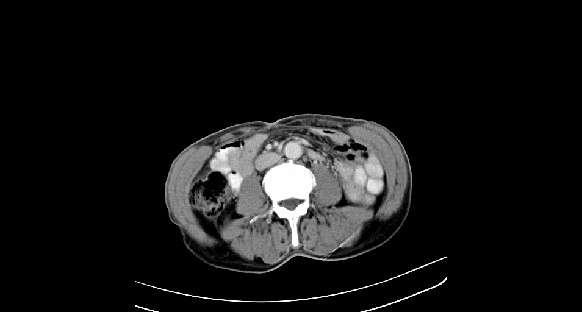

男性,70岁,体检b超发现左肾占位,请各位战友发表一下观点

左肾有两个病灶,且较大的病灶内可见点状钙化灶,增强扫描边缘也是呈渐进性强化,中央部分未见明显强化

肾癌较肾aml可能大,建议mri,若t2明显高信号者则肾癌基本诊断明确。